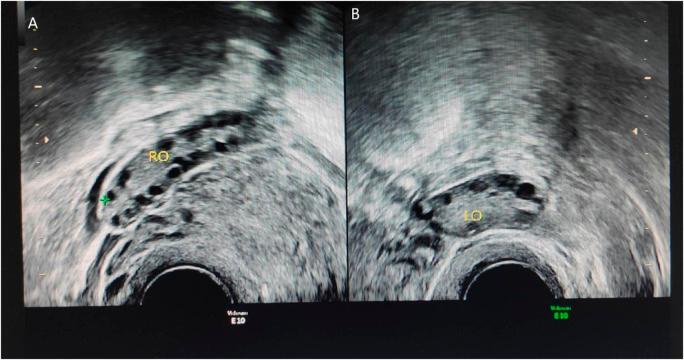

Based on whole-exome sequencing, six mutations residing in three genes were detected in these four patients: (1) located at Chr 3q29, (2) FSHD region gene 1 ()gene located at Chr 4q35.2, and (3) androgen receptor () located at Chr Xq11-q12 were detected in these four patients (every patients had the 6 mutations). Of the six genetic mutations, an insertion/deletion (indel) mutation was found in the mucin 4 () gene [MUC4:NM_018406.6:2/25:c.7701_7702insTCAGTATCCACAGGTCATGCCACCCCTCTTCATGTCACCGACACTTCC:p.(Ser2567_Ala2568insSerValSerThrGlyHisAlaThrProLeuHisValThrAspThrSer)], and an indel mutation in the gene (:NM_000044:exon1:c.173_174insGCAGCA:p. Q58delinsQQQ), while the other four were missense single-nucleotide polymorphisms (SNPs) located in of uncertain significance (:NM_004477:exon8:c.T692C:p. L231P, :NM_004477:exon8:c.C728T:p.T243M, :NM_004477:exon8:c.C733A:p.L245M, FRG1:NM_004477:exon8:c.T734G:p.L245R). A Mucin 4 () gene indel mutation was detected at the same site in four patients, which could be associated with endometriosis-related infertility. The gene indel mutation, :NM_000044:exon1:c.173_174insGCAGCA: p. Q58delinsQQQ was detected simultaneously in four patients.

基于全外显子测序,在这4例患者中检测到位于3个基因的6个突变:(1)位于3号染色体长臂29区,(2)位于4号染色体长臂35.2区的FSHD区域基因1()基因,以及(3)位于X染色体长臂11 - 12区的雄激素受体()在这4例患者中均被检测到(每位患者均有这6个突变)。在这6个基因突变中,在粘蛋白4()基因[MUC4:NM_018406.6:2/25:c.7701_7702insTCAGTATCCACAGGTCATGCCACCCCTCTTCATGTCACCGACACTTCC:p.(Ser2567_Ala2568insSerValSerThrGlyHisAlaThrProLeuHisValThrAspThrSer)]中发现一个插入/缺失(indel)突变,在基因(:NM_000044:exon1:c.173_174insGCAGCA:p. Q58delinsQQQ)中发现一个indel突变,而另外4个是位于意义不明确的(:NM_004477:exon8:c.T692C:p. L231P,:NM_004477:exon8:c.C728T:p.T243M,:NM_004477:exon8:c.C733A:p.L245M,FRG1:NM_004477:exon8:c.T734G:p.L245R)中的错义单核苷酸多态性(SNP)。在4例患者的同一位置检测到粘蛋白4()基因indel突变,这可能与子宫内膜异位症相关的不孕有关。基因indel突变,:NM_000044:exon1:c.173_174insGCAGCA: p. Q58delinsQQQ在4例患者中同时被检测到。